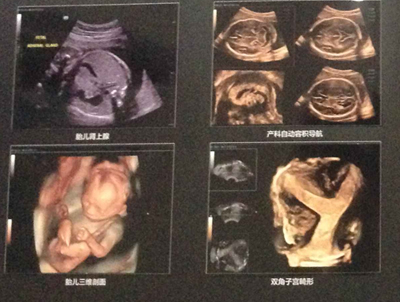

工欲善其事,必先利其器。近年来,杭州红房子妇产医院在不断加强医疗技术和服务质量的同时,还持续加大医疗设备等硬件的建设与投入。近日,斥资引进的迈瑞Reson6高端四维彩超,具有全域动态聚焦、实时弹性成像技术、自动卵泡监测等众多优点,与传统超声系统相比,不仅显著缩短了检查时间,还能在视觉上更为清晰、直观地观察到子宫、卵巢、附件等盆腔器官的异常,被誉为“妇科临床彩超检查的火眼金睛”。

据悉,目前杭州红房子妇产医院拥有“妇科微创手术黄金组合”德国WOLF宫腹腔镜、“人流术后恢复专家”ZHE保宫仪、“私密抗衰领域的法拉利”Femilift菲蜜丽私密激光等一大批现代化的医疗设备,为医院学科发展提供良好的硬件基础。随着迈瑞Reson6高端四维彩超的投入使用,将进一步提升医院的临床诊断水平,为广大女性朋友在进行妇科疾病检查时,及时、准确、高效的临床诊断提供丰富精确的诊疗依据。